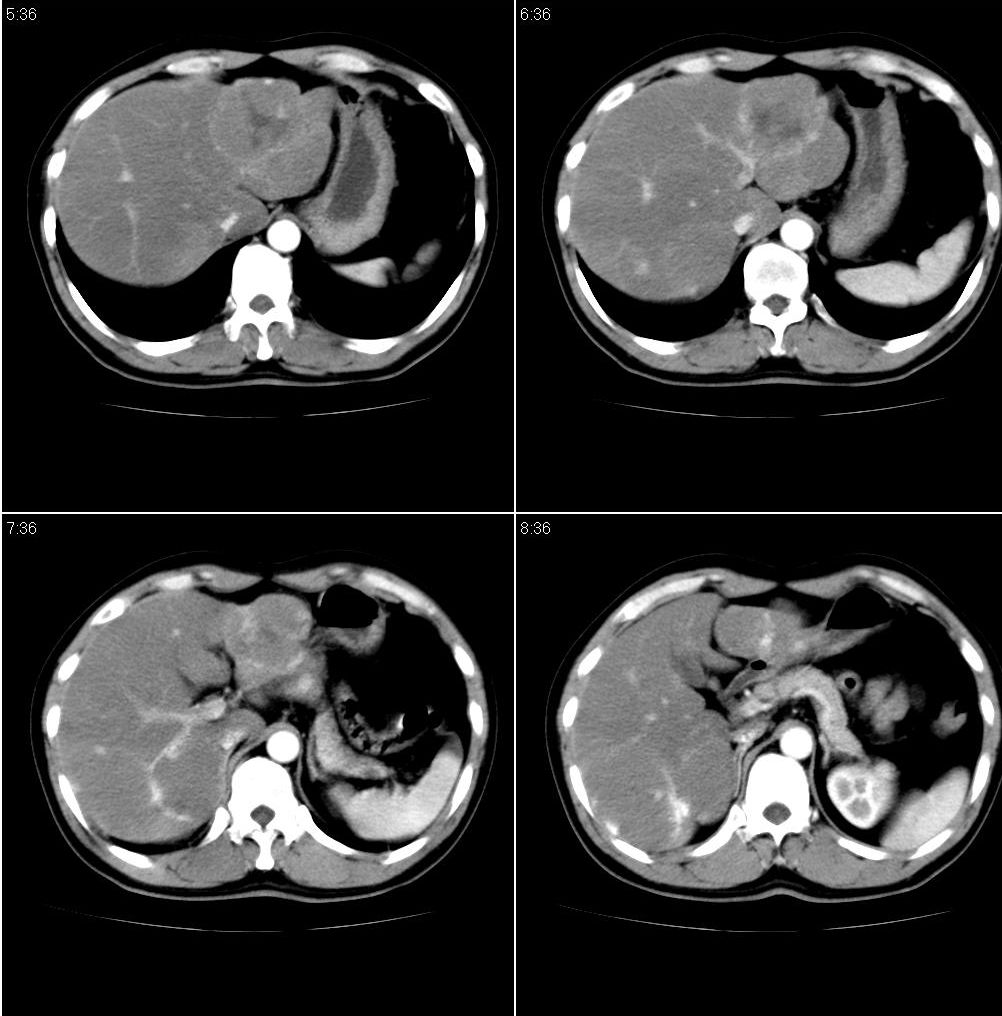

男,43岁。体检发现肝脏病变

肝局灶性脂肪肝 肝左叶外侧段占位病变,建议加强

考虑肝左叶癌并脂肪肝,肿块在脂肪肝衬托下呈高密度影,其内可见坏死灶,建议增强

肝右叶密度均匀减低,左叶增大,表面凹凸不平,内有低密度影。脾不大其密度较肝稍高。考虑1脂肪肝2肝左叶占位。建议增强。

1)局灶性脂肪肝2)肝左叶外侧段内占位,建议强化

肝局灶性脂肪肝 肝左叶外侧段1)肝海绵状血管瘤2)肝ca

肝右叶密度均匀减低,左叶增大,表面凹凸不平,内有低密度影。考虑1局灶性脂肪肝 2肝左叶占位。建议增强。

下缘与胃窦关系密切,会不会是来源于胃的间质瘤??